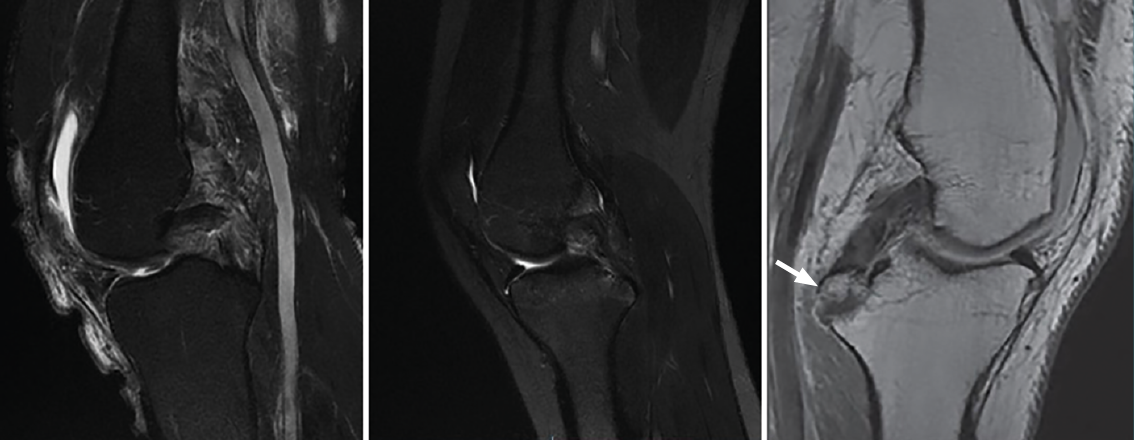

Magnetic resonance imaging

Although the diagnosis of PCL rupture is essentially clinical, and instability is quantified from stress radiographs, magnetic resonance imaging (MRI) is the technique of choice for the diagnosis and follow-up of PCL lesions subjected to conservative management, and affords excellent information on the presence of associated injuries - not only ligament damage but also meniscal or chondral lesions. In addition, MRI is able to distinguish between acute and chronic injuries, since the absence of soft tissue edema and of bone contusion (usually affecting the anterior portion of the tibia) is indicative of a chronic lesion(13,14).

Posterior cruciate ligament injuries are divided into three types according to their MRI characteristics: partial or intrasubstance lesions (Figure 6A), complete lesions (Figure 6B) and avulsion fractures at the tibial insertion (Figure 6C)(13,14). Most complete lesions occur in the middle portion of the ligament, which is not correctly visualized in the axial and coronal planes; the gold standard therefore is evaluation of images in the sagittal plane(13,14).

Figure 6. A: magnetic resonance imaging (MRI) sagittal view in T2-weighted sequencing, showing partial rupture; B: complete rupture of the posterior cruciate ligament (PCL); C: MRI sagittal view in T1-weighted sequencing of the left knee. The white arrow indicates avulsion of the PCL with a bone fragment in the tibial insertion.